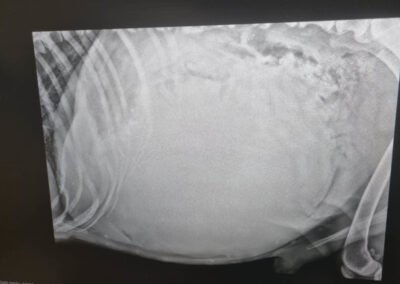

Die Untersuchungen beim Tierarzt haben leider ergeben, dass er einen Milztumor hat und der Krebs bei Dedo bereits so weit fortgeschritten ist, dass eine Operation keinen Sinn mehr ergeben würde. Die Narkose wäre für ihn ein zu großes Risiko, und wir wollen ihm unnötiges Leiden ersparen. Stattdessen haben wir beschlossen, Dedo seine letzten Tage, Wochen oder Monate so angenehm wie möglich zu gestalten. Dedo darf nun bei unserer Tierschützerin vor Ort im Zwinger leben, da er das Leben draußen gewohnt ist und drinnen nicht bleiben möchte. Sie sorgt liebevoll für ihn und kocht ihm sogar seine Mahlzeiten selbst – eine kleine Freude, die ihm in dieser schweren Zeit geblieben ist. Bitte helft uns, Dedo die letzten Momente seines Lebens so schön wie möglich zu machen. Eine Futter- oder Medizinpatenschaft würde uns sehr helfen, damit wir Dedo in seiner letzten Zeit angemessen versorgen können.